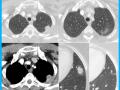

Diagnóstico por imagem em ginecologia - Quinto ano medicina